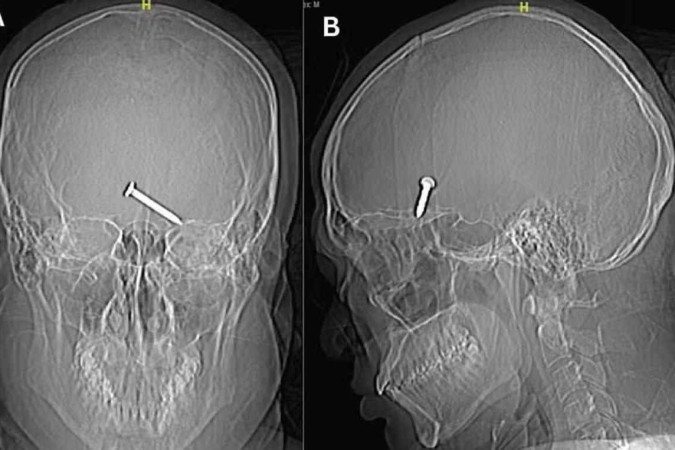

Um raio-x do crânio mostrou que o prego de três centímetros havia se alojado no cérebro do homem. Uma parte do crânio foi quebrada pelo impacto. No hospital, apesar da gravidade do ferimento, a vítima apresentava bons sinais vitais.